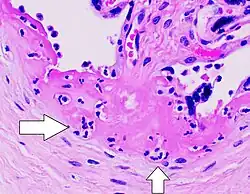

| Gross pathology of severe intervillositis, with dark red and soggy tissue. | |

Chronic Histiocytic Intervillositis (CHI or CHIV) also known as Chronic Intervillositis of Unknown (A)etiology (CIUE) and Massive Chronic Intervillositis (MCI) is defined as a diffuse infiltration of mononuclear cells (histiocytes, lymphocytes, monocytes) of maternal origin into the intervillous space within the placenta. It often results in severe intrauterine growth restriction which can lead to miscarriage or stillbirth. Overall perinatal mortality rate is high: 41%[6] to 77%.[7] Recurrence rate is also high: 67%[7] to 100%.[6]